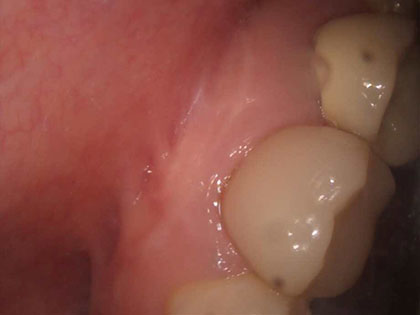

• 術前の写真がこちら

• 歯根端切除の術前1

• 歯根端切除の術前2

• 歯根端切除の術前3

• 歯根端切除の術前4

• 歯根端切除の術前5